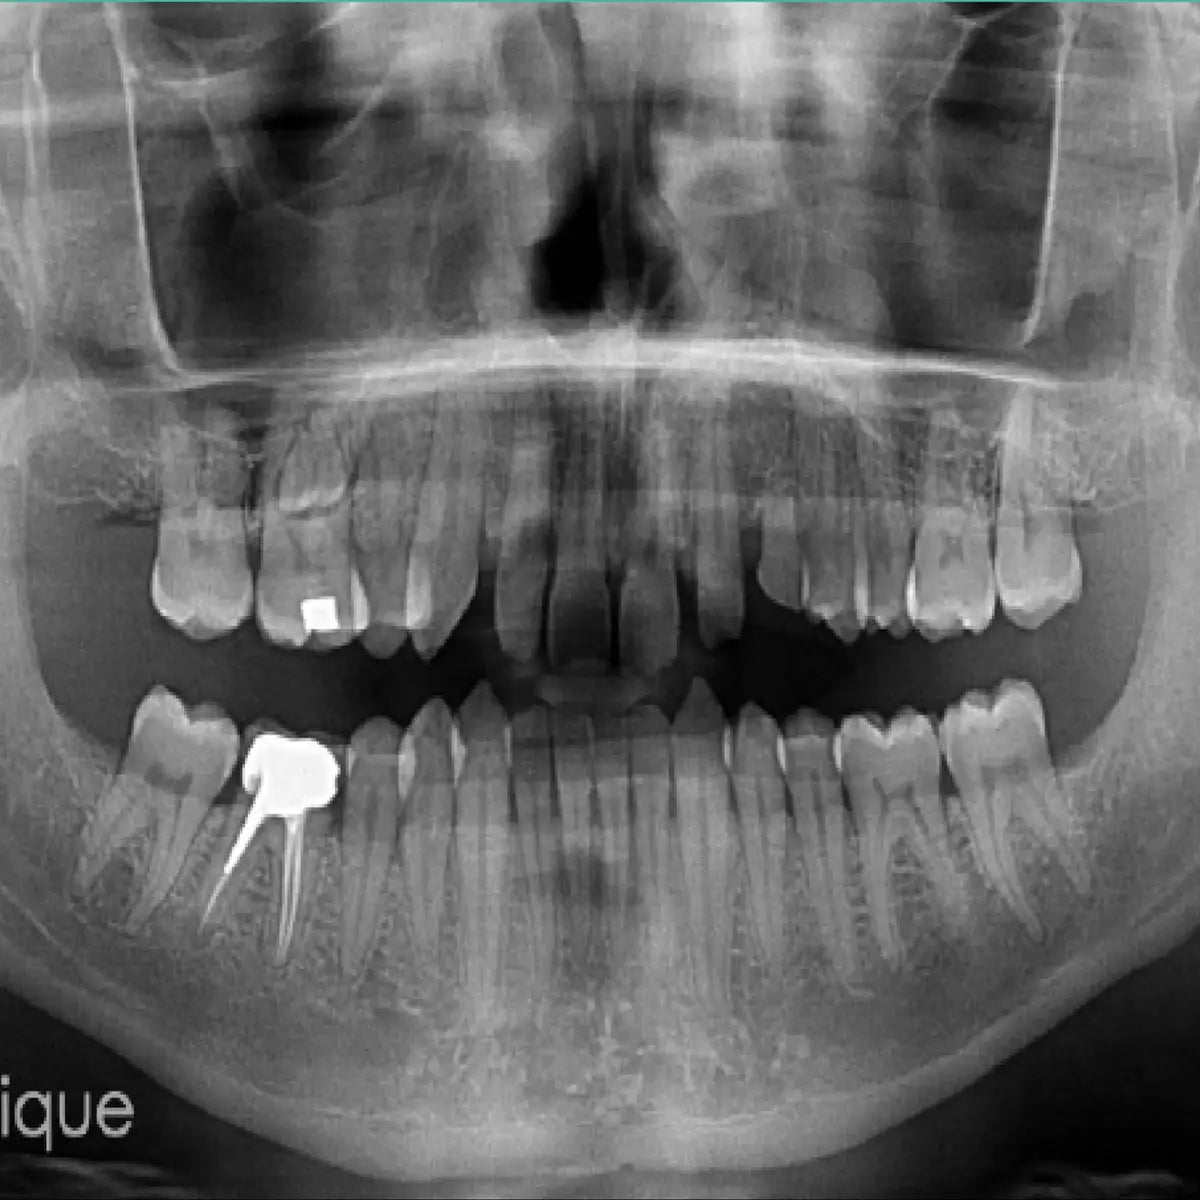

Le Cone Beam Computed Tomography (CBCT), ou imagerie volumique à faisceau conique, a profondément transformé la radiologie dentaire.

Il permet une visualisation tridimensionnelle précise des structures dento-maxillaires, offrant au praticien un outil diagnostique et préchirurgical de très haute fiabilité.